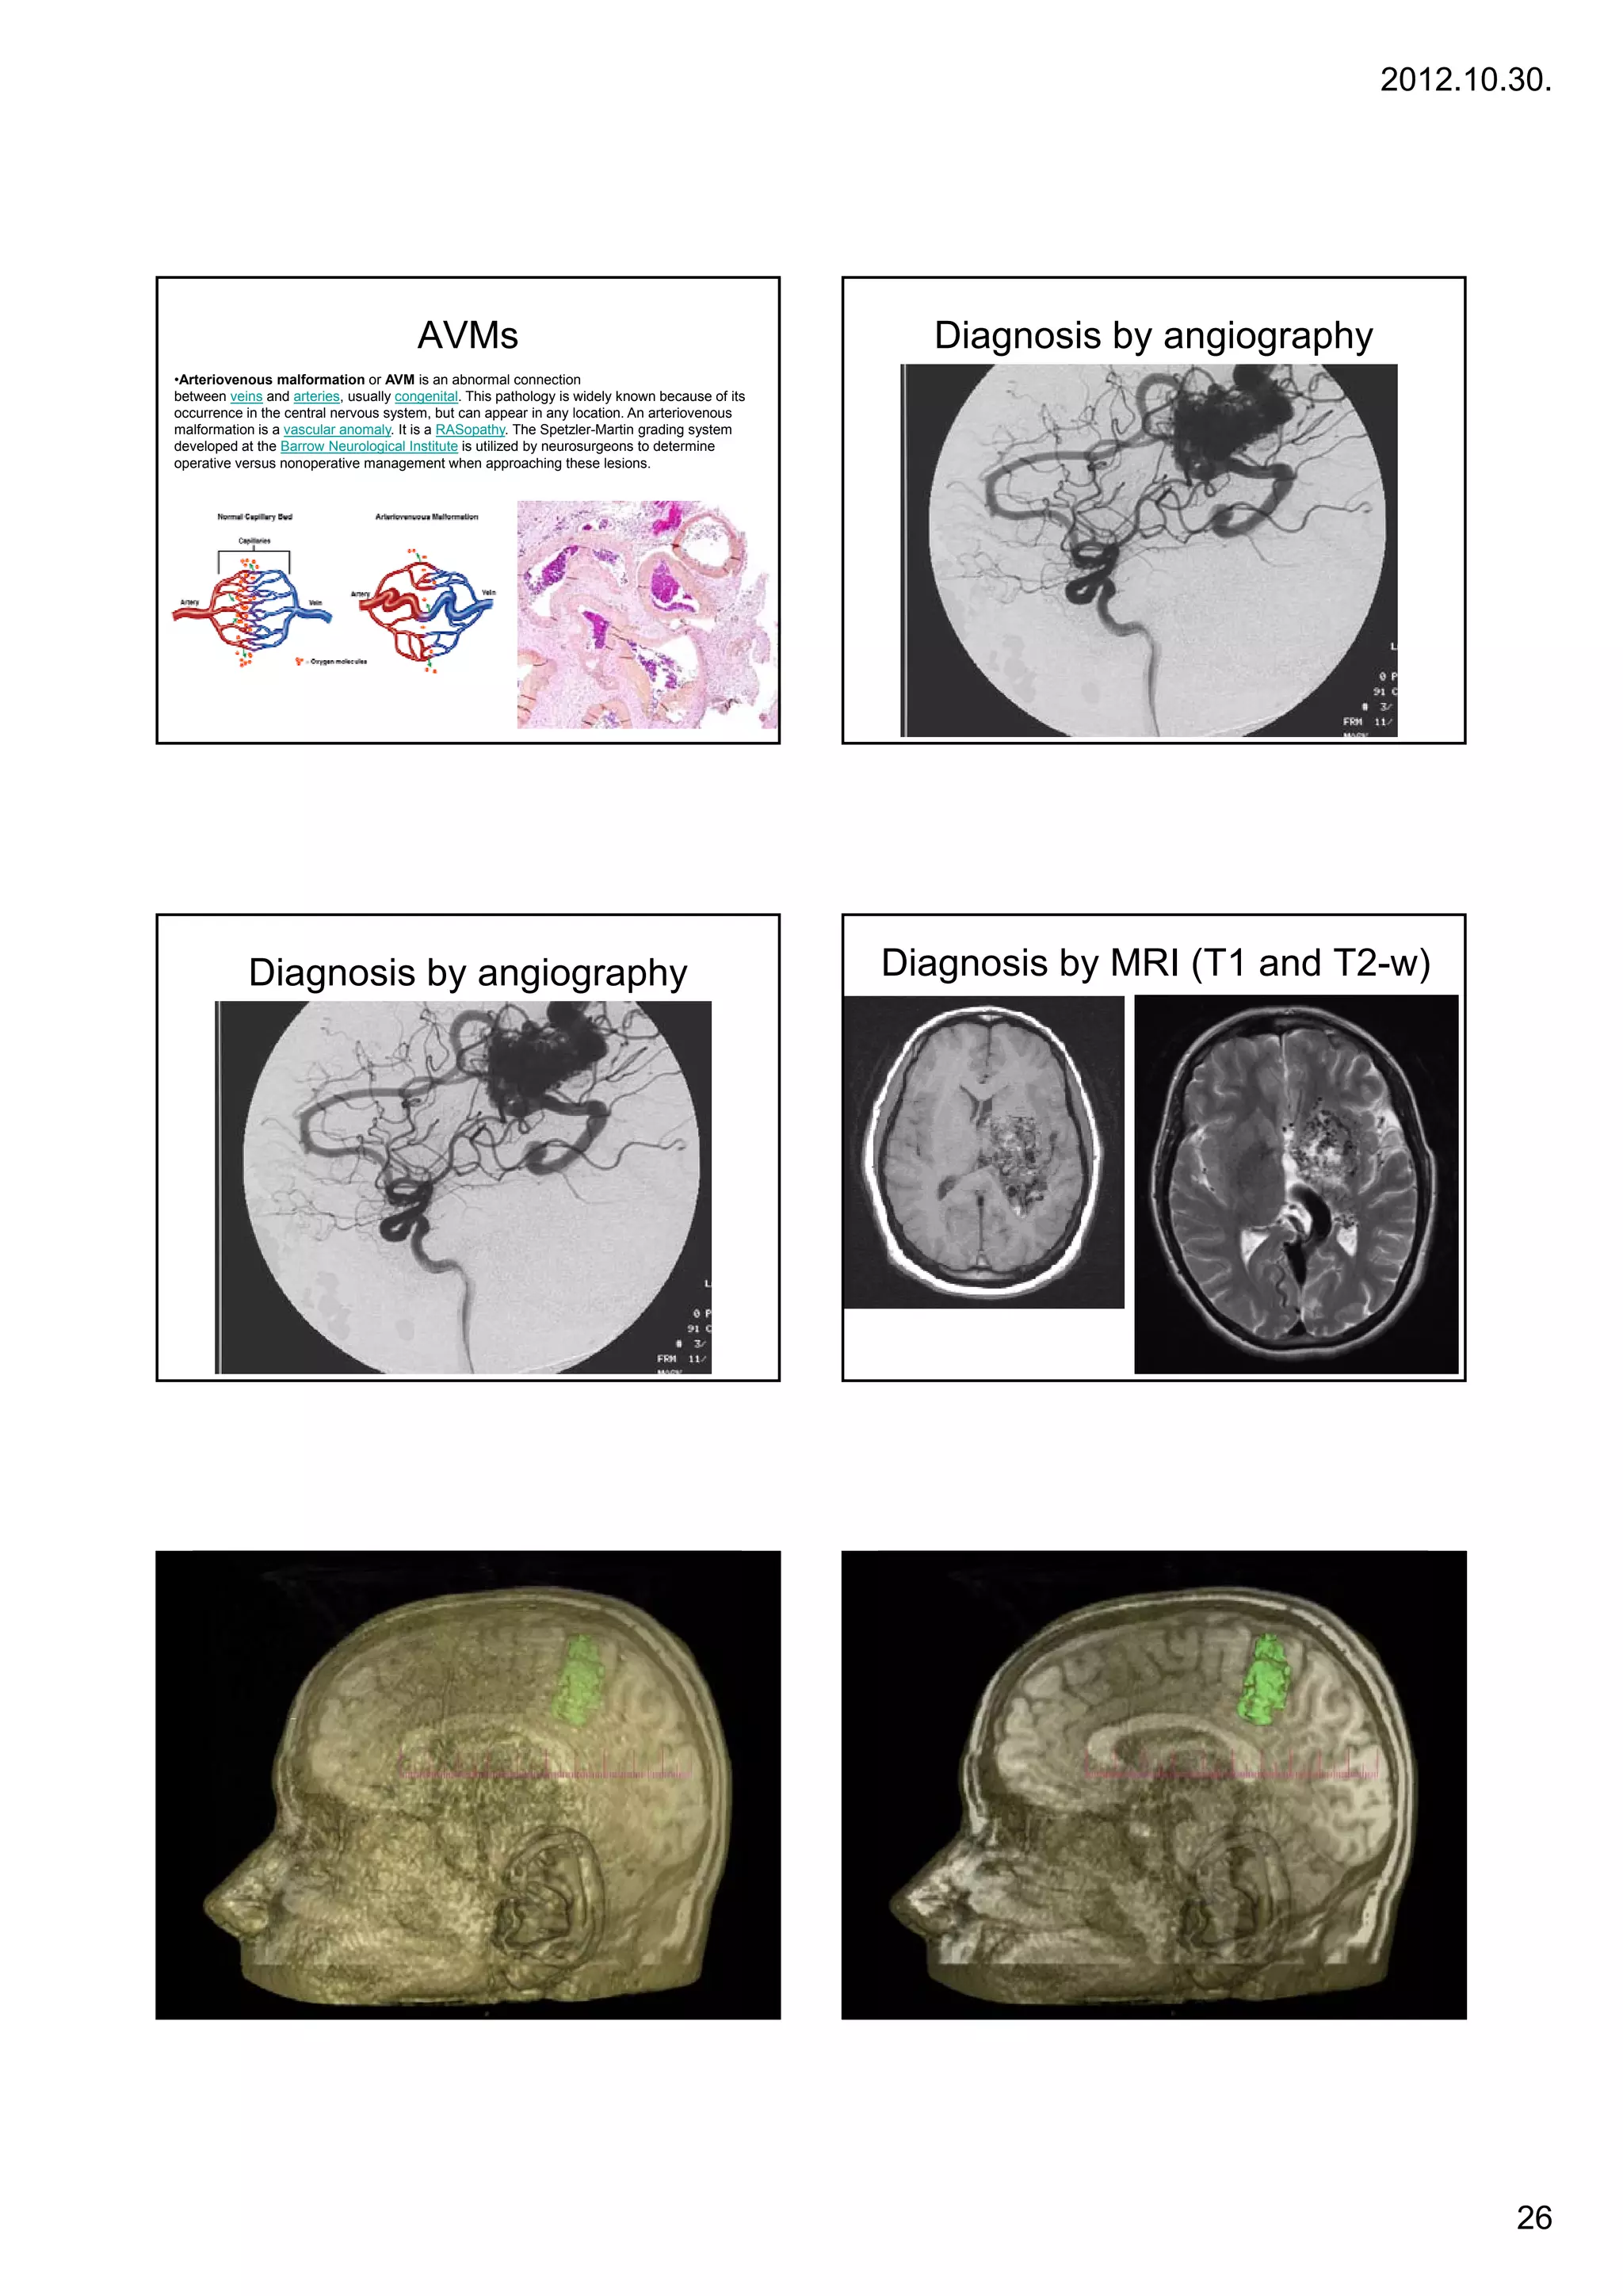

AVMs                                                       Diagnosis by angiography

•Arteriovenous malformation or AVM is an abnormal connection

between veins and arteries, usually congenital. This pathology is widely known because of its

occurrence in the central nervous system, but can appear in any location. An arteriovenous

malformation is a vascular anomaly. It is a RASopathy. The Spetzler-Martin grading system

developed at the Barrow Neurological Institute is utilized by neurosurgeons to determine

operative versus nonoperative management when approaching these lesions.

Diagnosis by angiography                                                            Diagnosis by MRI (T1 and T2-w)